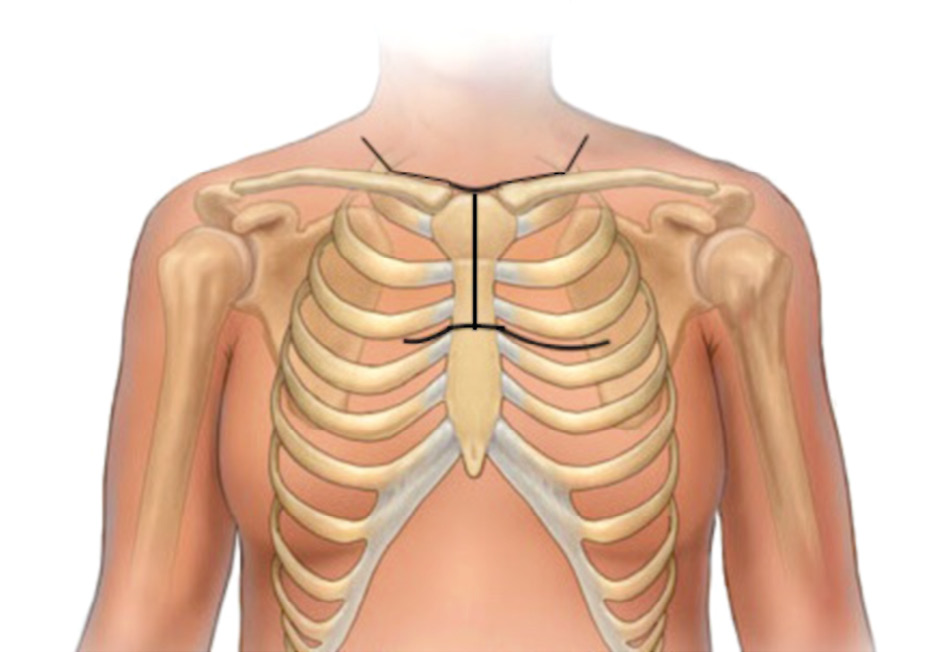

На операции: выполнен Т-образный разрез, грудина пересечена на уровне средней трети тела, доступ дополнен торакотомией слева по III межреберью (рис. 4).

Рис. 4. Операционный доступ. / Fig. 4. Surgical access.